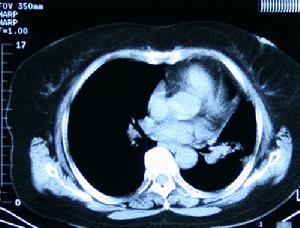

3.CT檢查 在十二指腸部位有界限清楚的實質性腫塊影,若腫瘤內有對比造影劑和氣體,更有助於診斷增強掃描為中等血供或血供較豐富的腫瘤,應與胰頭部腫瘤鑑別。